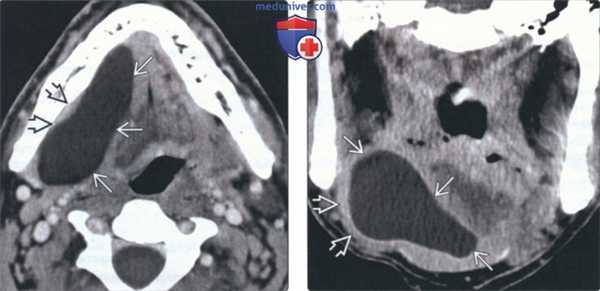

(Слева) КТ с КУ, аксиальная проекция. Крупная простая ранула В, деформирующая правое подъязычное пространство и смещающая челюстно-подъязычную мышцу в латеральную сторону. Утолщения стенок или накопления в них контраста нет, что говорит об отсутствии воспаления.

(Справа) КТ с КУ, коронарная проекция. Челюстно-подъязычная мышца В смещена книзу и латерально крупной, тонкостенной однокамерной кистой В. Простая ранула выглядит идентично эпидермоидной кисте подъязычного пространства. Для постановки диагноза требуется биопсия или четкий анамнез (при врожденной кисте).

(Слева) На аксиальной КТ с КУ определяется большая ПР, растягивающая правую ПЯЖ и приводящая к дугообразному выбуханию челюстно-подъязычной мышцы кнаружи. Заметное контрастное усиление или утолщение стенки кисты отсутствует, как и воспалительные изменения окружающих тканей.

(Справа) На корональной КТ с КУ в отсроченной фазе у этого же пациента определяется дугообразное выбухание челюстно-подъязычной мышцы книзу и кнаружи, обусловленное крупной однокамерной кистой с тонкой стенкой. ПР выглядит идентично эпидермоиду ПЯП, поэтому для установления окончательного диагноза требуется патоморфологическое исследование или точные данные о врожденной природе образования.